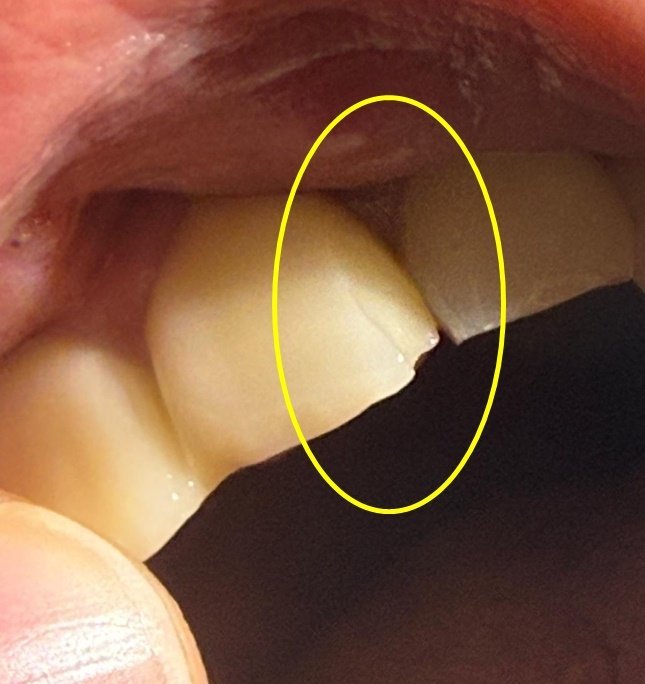

공개된 사진에는 사고 당시 피해자의 앞니가 일부 깨져 나간 모습이 담겼다. 앞니 끝이 강한 이물질과 부딪쳤음을 짐작하게 한다.

치과 관련 종사자라고 밝힌 한 누리꾼은 “앞니는 크라운 치료가 필요한 경우가 많다”며 “치료 과정의 통증과 향후 재치료 가능성까지 고려해야 한다. 기능뿐 아니라 외관 문제까지 동반되는 만큼 단순 치료비만으로 끝낼 사안이 아니다”라고 설명했다.